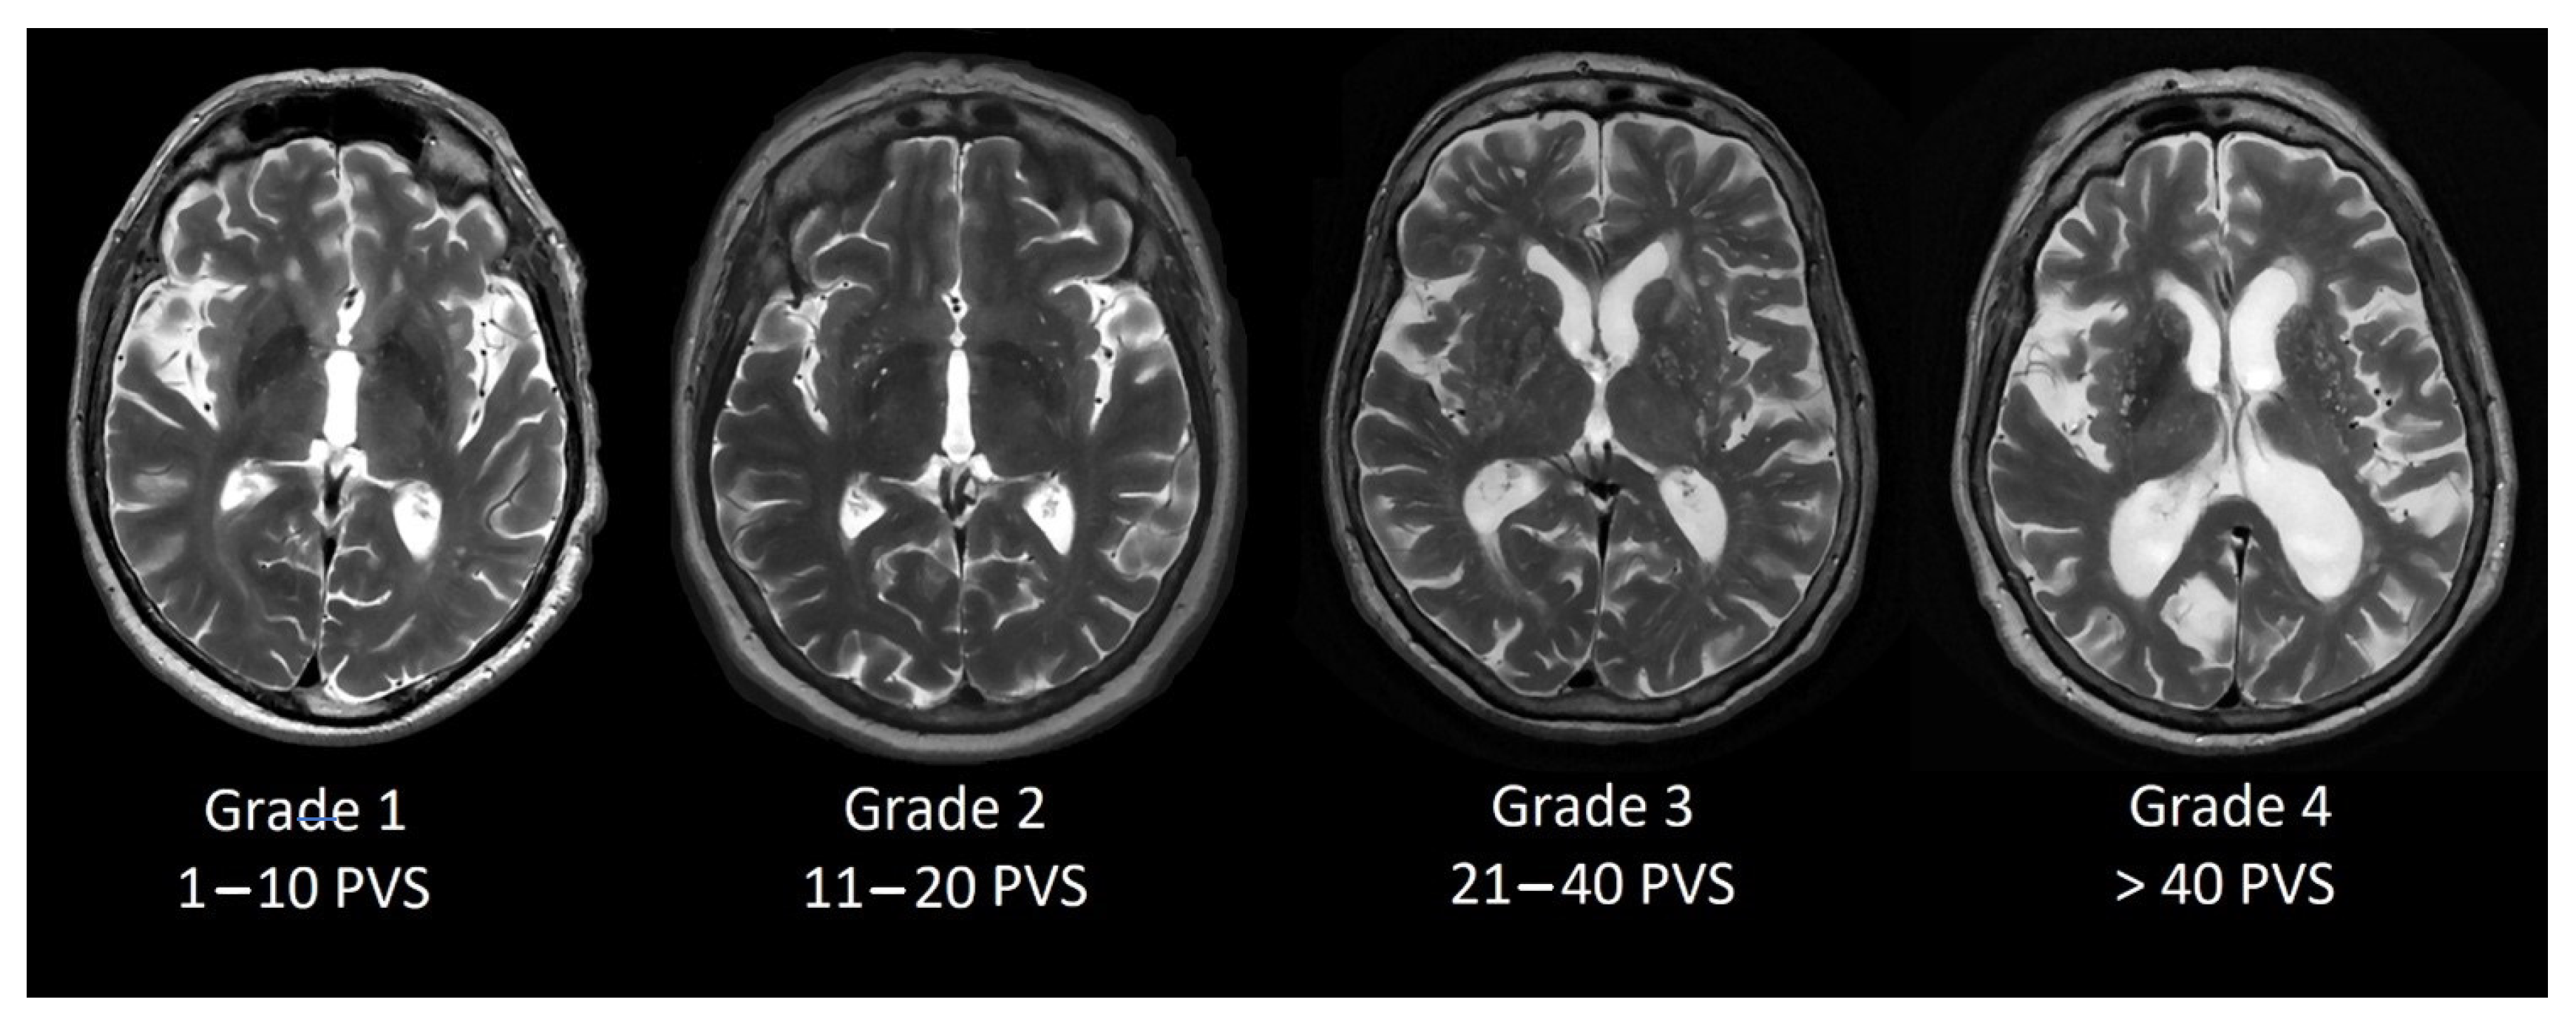

Perivascular space grading was partially based on Potter et al. [13] grading scale. We evaluated basal ganglia PVS (Type 1, see Figure 1) and centrum semiovale PVS (Type 2, see Figure 2) by the rating scale: grade 0–no PVS dilatation; Grade 1–1 to 10 dilatated PVS; Grade 2–11 to 20 dilatated PVS; Grade 3–21 to 40 dilatated PVS; Grade 4–>40 dilatated PVS.

Figure 1. Dilated PVS in basal ganglia from Grade 1 to Grade 4.